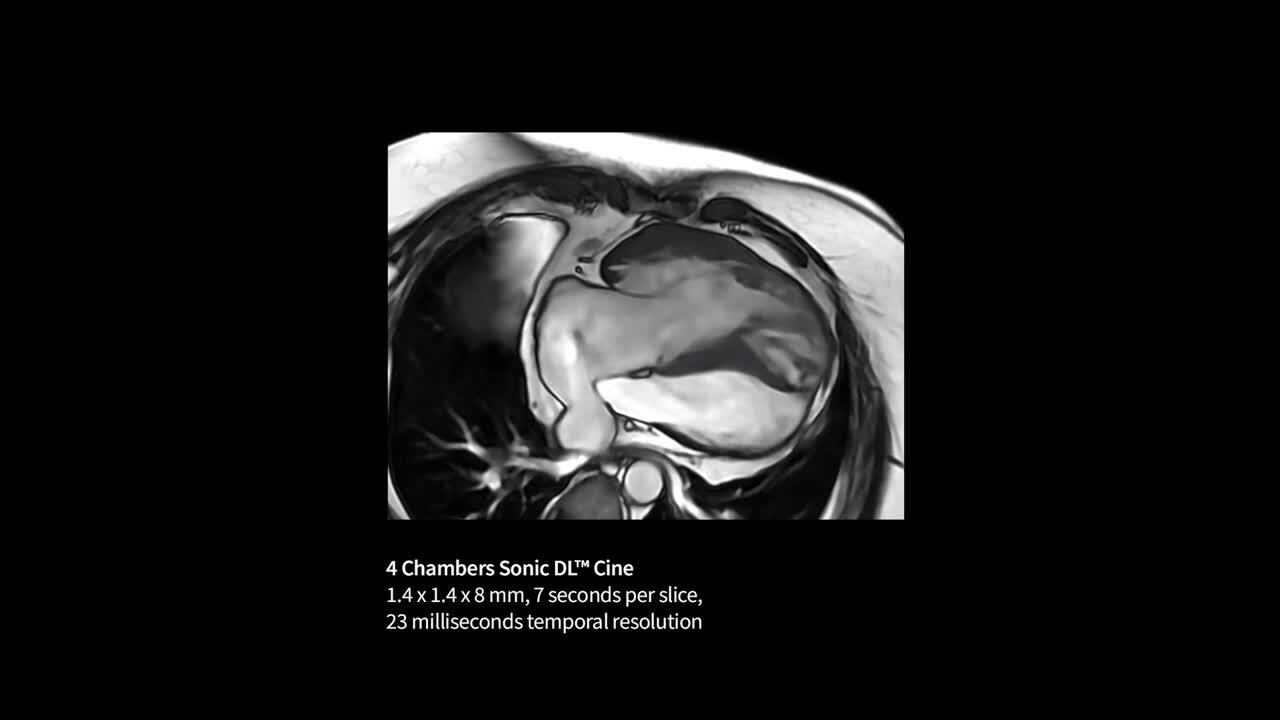

Capture clarity

Improve SNR and image sharpness by up to 60% with AIR™ Recon DL

Life-Speed imaging

Achieve up to 12X acceleration and up to 83% scan time reduction*